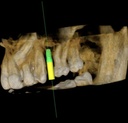

Introducing the CS 9300 Premium Panoramic, Cephalometric, and Cone Beam System from Carestream Dental – your ultimate solution for top-quality dental imaging. This state-of-the-art machine offers both 2D panoramic and cephalometric dental X-rays, as well as adjustable 3D cone beam images in up to seven different field of view sizes, extending up to 17x13.5 cm. This comprehensive range of imaging capabilities makes it a versatile tool, perfect for supporting a wide array of dental, surgical, or orthodontic examinations.

With the CS 9300 Premium, you can expect unparalleled image clarity and precision, allowing you to confidently diagnose and plan treatments with ease. Whether you're performing routine dental check-ups, complex surgical procedures, or orthodontic assessments, this system ensures outstanding results.

The CS 9300's 2D panoramic x-ray imaging capabilities are powered by variable focal trough technology, which provides optimal clarity for every image. The system's 3D imaging capabilities are based on cone beam technology, which delivers high-resolution images with a low radiation dose.

- Endodontics

- Implantology